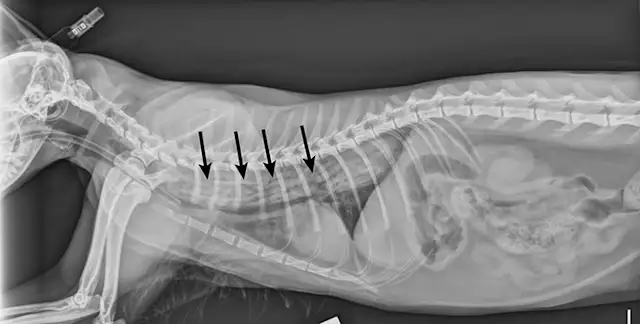

FIGURE 1A

Lateral view. Abdominal radiographs showing a rock foreign body that appears to be located in the small intestine. No small intestinal foreign body could be located on abdominal ultrasound; however, a shadowing foreign object was possibly located in the stomach.